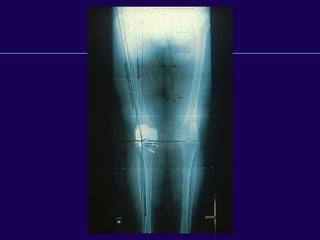

Complications in Total

Knee Arthroplasty

Periprosthetic Fractures

Supracondylar

Fractures of the

Femur

After Total Knee

Arthroplasty

Supracondylar Fractures

After TKR